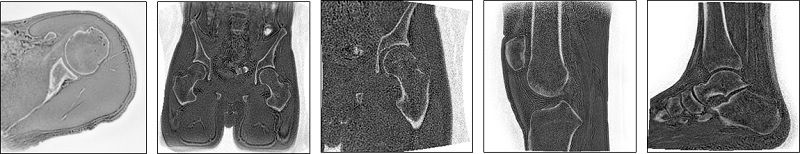

Figure 1. Example of oZTEo images

oZTEo (MR Bone) is a type-in, 3D, Gradient Echo, Fast SPGR sequence that uses a ZTE (zero TE) Acquisition for 3D k-space data acquired in radial trajectories. It creates images with bright bone signal, flat soft tissue, and an inverted grayscale.

oZTEo (MR Bone) is useful for post-processing with MR General Review for better visualization of bone surfaces.